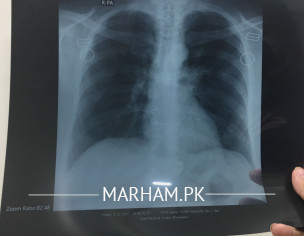

Can somebody please read this CT scan to me? Even if it’s not clear please give me an idea of what you can get? I cannot get in touch with a radiologist or pulmonologist for some reason. The scan was taken on 8th day of COVID. The patient is diabetic, oxygen varies from 97-93 but it’s mostly because she has severe cough. Today is 10th day of COVID. She is taking azomax 250 mg, cough syrup, ascard and panadol. Attaching X-ray too. Her Serum CRP is at 4.62 and D-Dimmer is 135. She has no breathing issue. Just severe cough and high fever around 100/101.

there is some consolidation in lower zone only